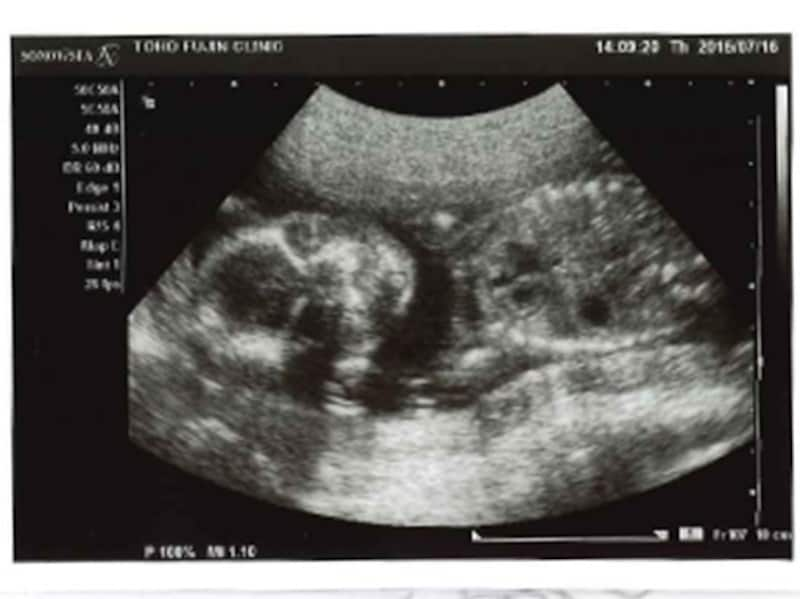

妊娠20週(20w)の時期は、赤ちゃんの記憶と思考機能の発達に必要な、複雑な神経のネットワークがぐんぐん成長。また、赤ちゃんが股を開いていれば、超音波検査で性別が分かる頃です。

妊娠20週目エコー写真・胎児の大きさや胎動の様子・性別